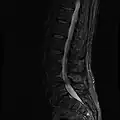

MRI

-

MRI lumbar spine with degeneration (sagittal T2 FRFSE) -

MRI lumbar spine with degeneration (sagittal T1 FSE) -